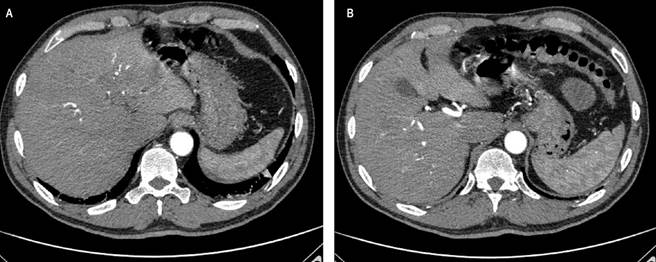

An upper digestive endoscopy (UDE) was performed to rule out any lesions that could explain the pneumatosis findings. The only abnormality identified was mucosal pallor of the gastric body, antrum, and duodenum, with erosions but no ulcers, consistent with signs of mild ischemia (Figure 3). Based on these findings, a CT angiography was conducted, which ruled out vascular ischemic involvement of the esophagus, stomach, duodenum, or intestines and confirmed vascular patency of the arterial and venous axes (Figure 4). Additionally, the resolution of the portal venous gas and improvement in the gastric pneumatosis were observed.